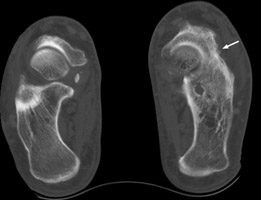

Calcaneonavicular coalition

Plain film and CT images of calcaneonavicular coalition. Notice the elongated, tubular like extension of the anterior calcaneus seen on the lateral film; this imagery has been likened to the elongated nose of an anteater. There is abnormal bony fusion of the calcaneus and navicular bones, with the presence of a bony bar extending between these two bones.

- Click on the image for a larger versionALateral foot - Click on the image for a larger versionBCT - Click on the image for a larger versionC